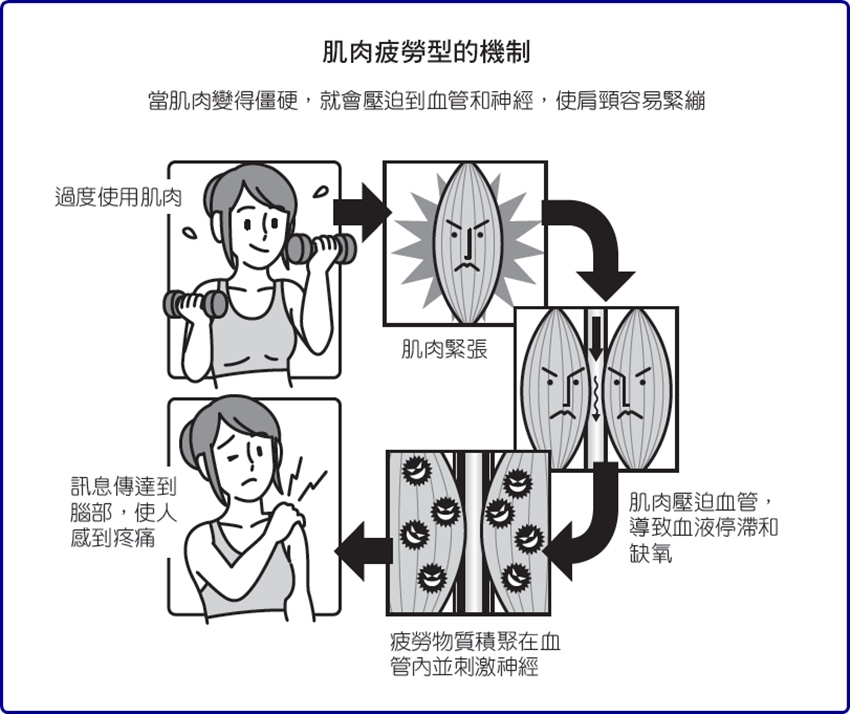

肌肉疲勞型

當我們在工作、家事和運動等方面大量使用肌肉,就會使肩膀周圍的肌肉變得僵硬緊繃。

如果只是一時性的過度使用那倒還好,但若以不良姿勢使用電腦,或是將長期累積的疲勞置之不理,就會變得難以擺脫這些僵硬和疼痛。